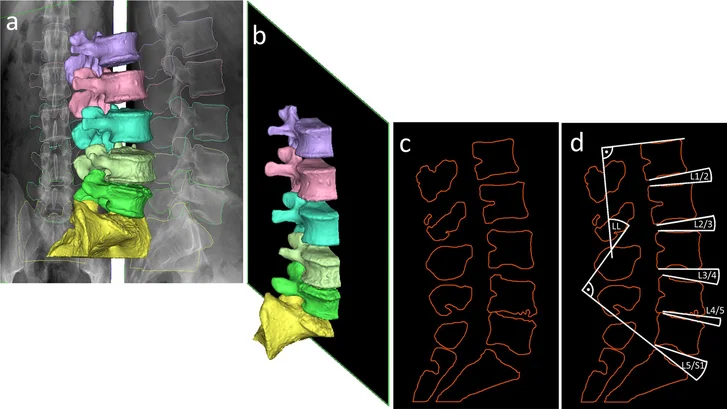

Az in silico egy tágabb fogalom, mi a biomechanikával kapcsolatos részére fókuszálunk. Tevékenységünk lényege, hogy képalkotó eljárásokból nyert információkkal olyan modelleket hozunk létre szoftverek által, amelyek elemei lehetnek egy probléma megértésének, megoldásának. Mi a gerincsebészetben MR és CT vizsgálatok eredményeit használjuk, de például a kardiológiában szintén nagyon előrehaladott az in silico eljárás, ott EKG és laboreredményeket is igénybe vesznek az orvosok.

Úgy kell elképzelni a folyamatot, hogy szoftveresen létrehozzuk a beteg avatárját, ami nagymértékben reprezentálja a páciens testi felépítését és fiziológiáját. A szakirodalom ezt digital twinnek, azaz digitális ikerpárnak nevezi. A virtuális beavatkozások ezen a modellen történnek: virtuális műtétet tudunk végrehajtani rajta, de például mechanikai terhelésnek is alá tudjuk vetni. A folyamat eredményeként a beteg számára optimális műtéti tervet tudunk kiválasztani több szcenárió közül.

A laboron belül külön entitásként kezeljük, és már megfogalmazódott a stratégiai döntés, hogy külön munkacsoport fog foglalkozni a mesterséges intelligenciával. A CT és MR felvételek alapján létrehozott modellek megalkotása komplex képfeldolgozó szoftverekkel történik, a munka nagy része automatizálható az AI algoritmusok segítségével. Az algoritmusok nemcsak automatizálnak, hanem folyamatosan tanulnak is, így egyre precízebben tudnak komplex problémákat megoldani. Nagyon sok mérnöki és kutatóorvosi munkaórát megspórolhat egy kifejlesztett, validált algoritmus.